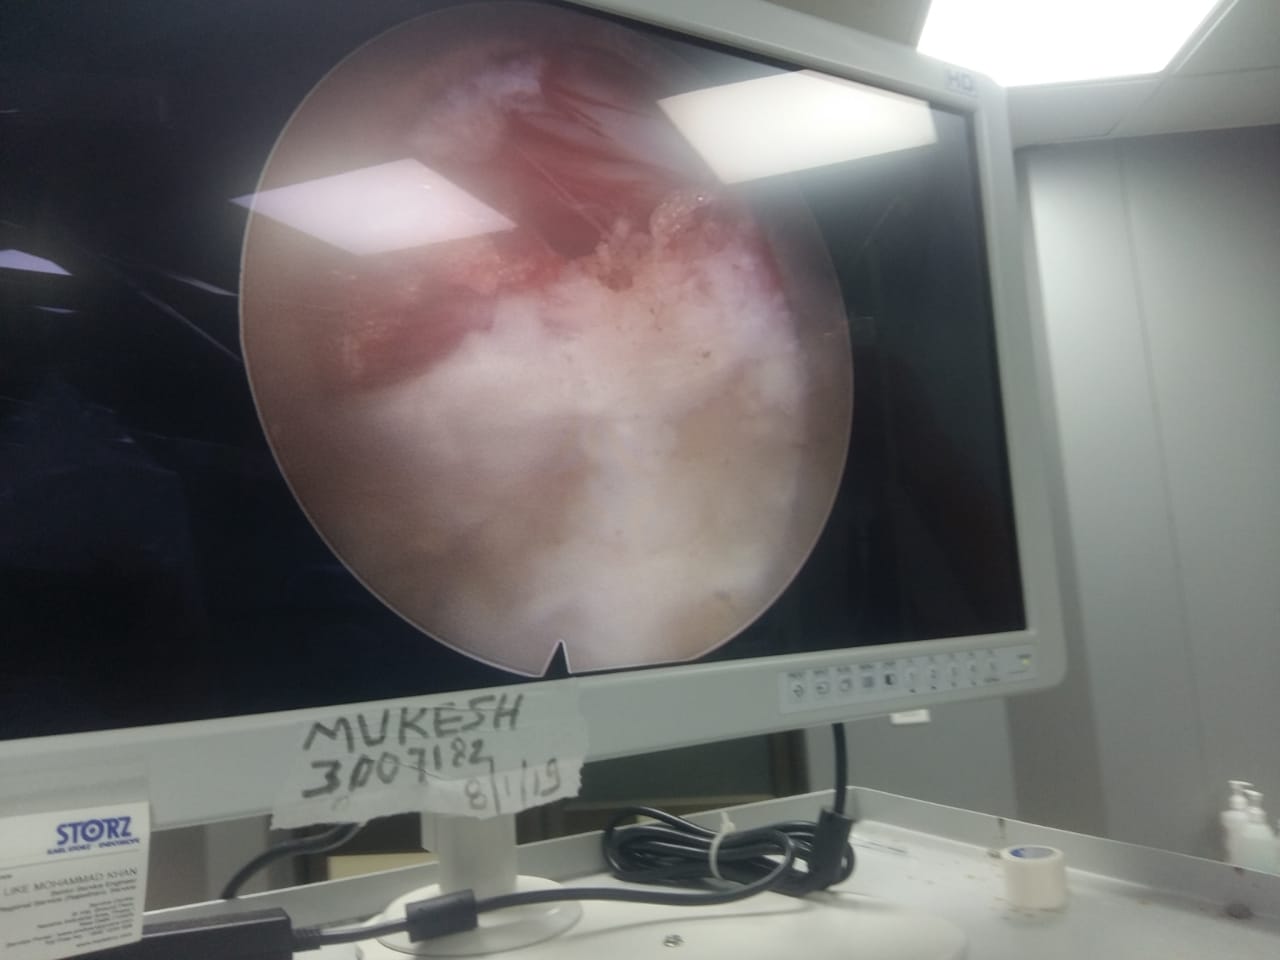

Endoscopic view of spinal canal

Endoscopic surgery in progress